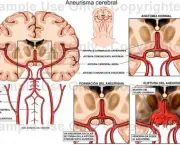

O Aneurisma Cerebral pode ser definido basicamente como uma dilatação anormal de uma das artérias do cérebro. Essa dilatação pode levar a ruptura dessa artéria, o que gera sangramentos que seguem para um espaço do cérebro chamado de “espaço subaracnóide”.

Em geral uma ruptura inicial de Aneurisma Cerebral leva cerca de 1/3 dos pacientes a morte, os que sobrevivem tem o risco de morte somado a cada novo episódio. O mais interessante a respeito do Aneurisma Cerebral e que poucos sabem é que muitas pessoas nascem com o aneurisma, o que os médicos chamam de Aneurisma Congênito.

Esse aneurisma pode aumentar e se romper, essas formações podem se romper em qualquer momento da vida, mas é mais comum na quarta ou quinta década da vida. As mulheres possuem mais chances de desenvolver aneurismas do que os homens e em mais de 20% dos pacientes é possível observar a existência de mais de um Aneurisma Cerebral.